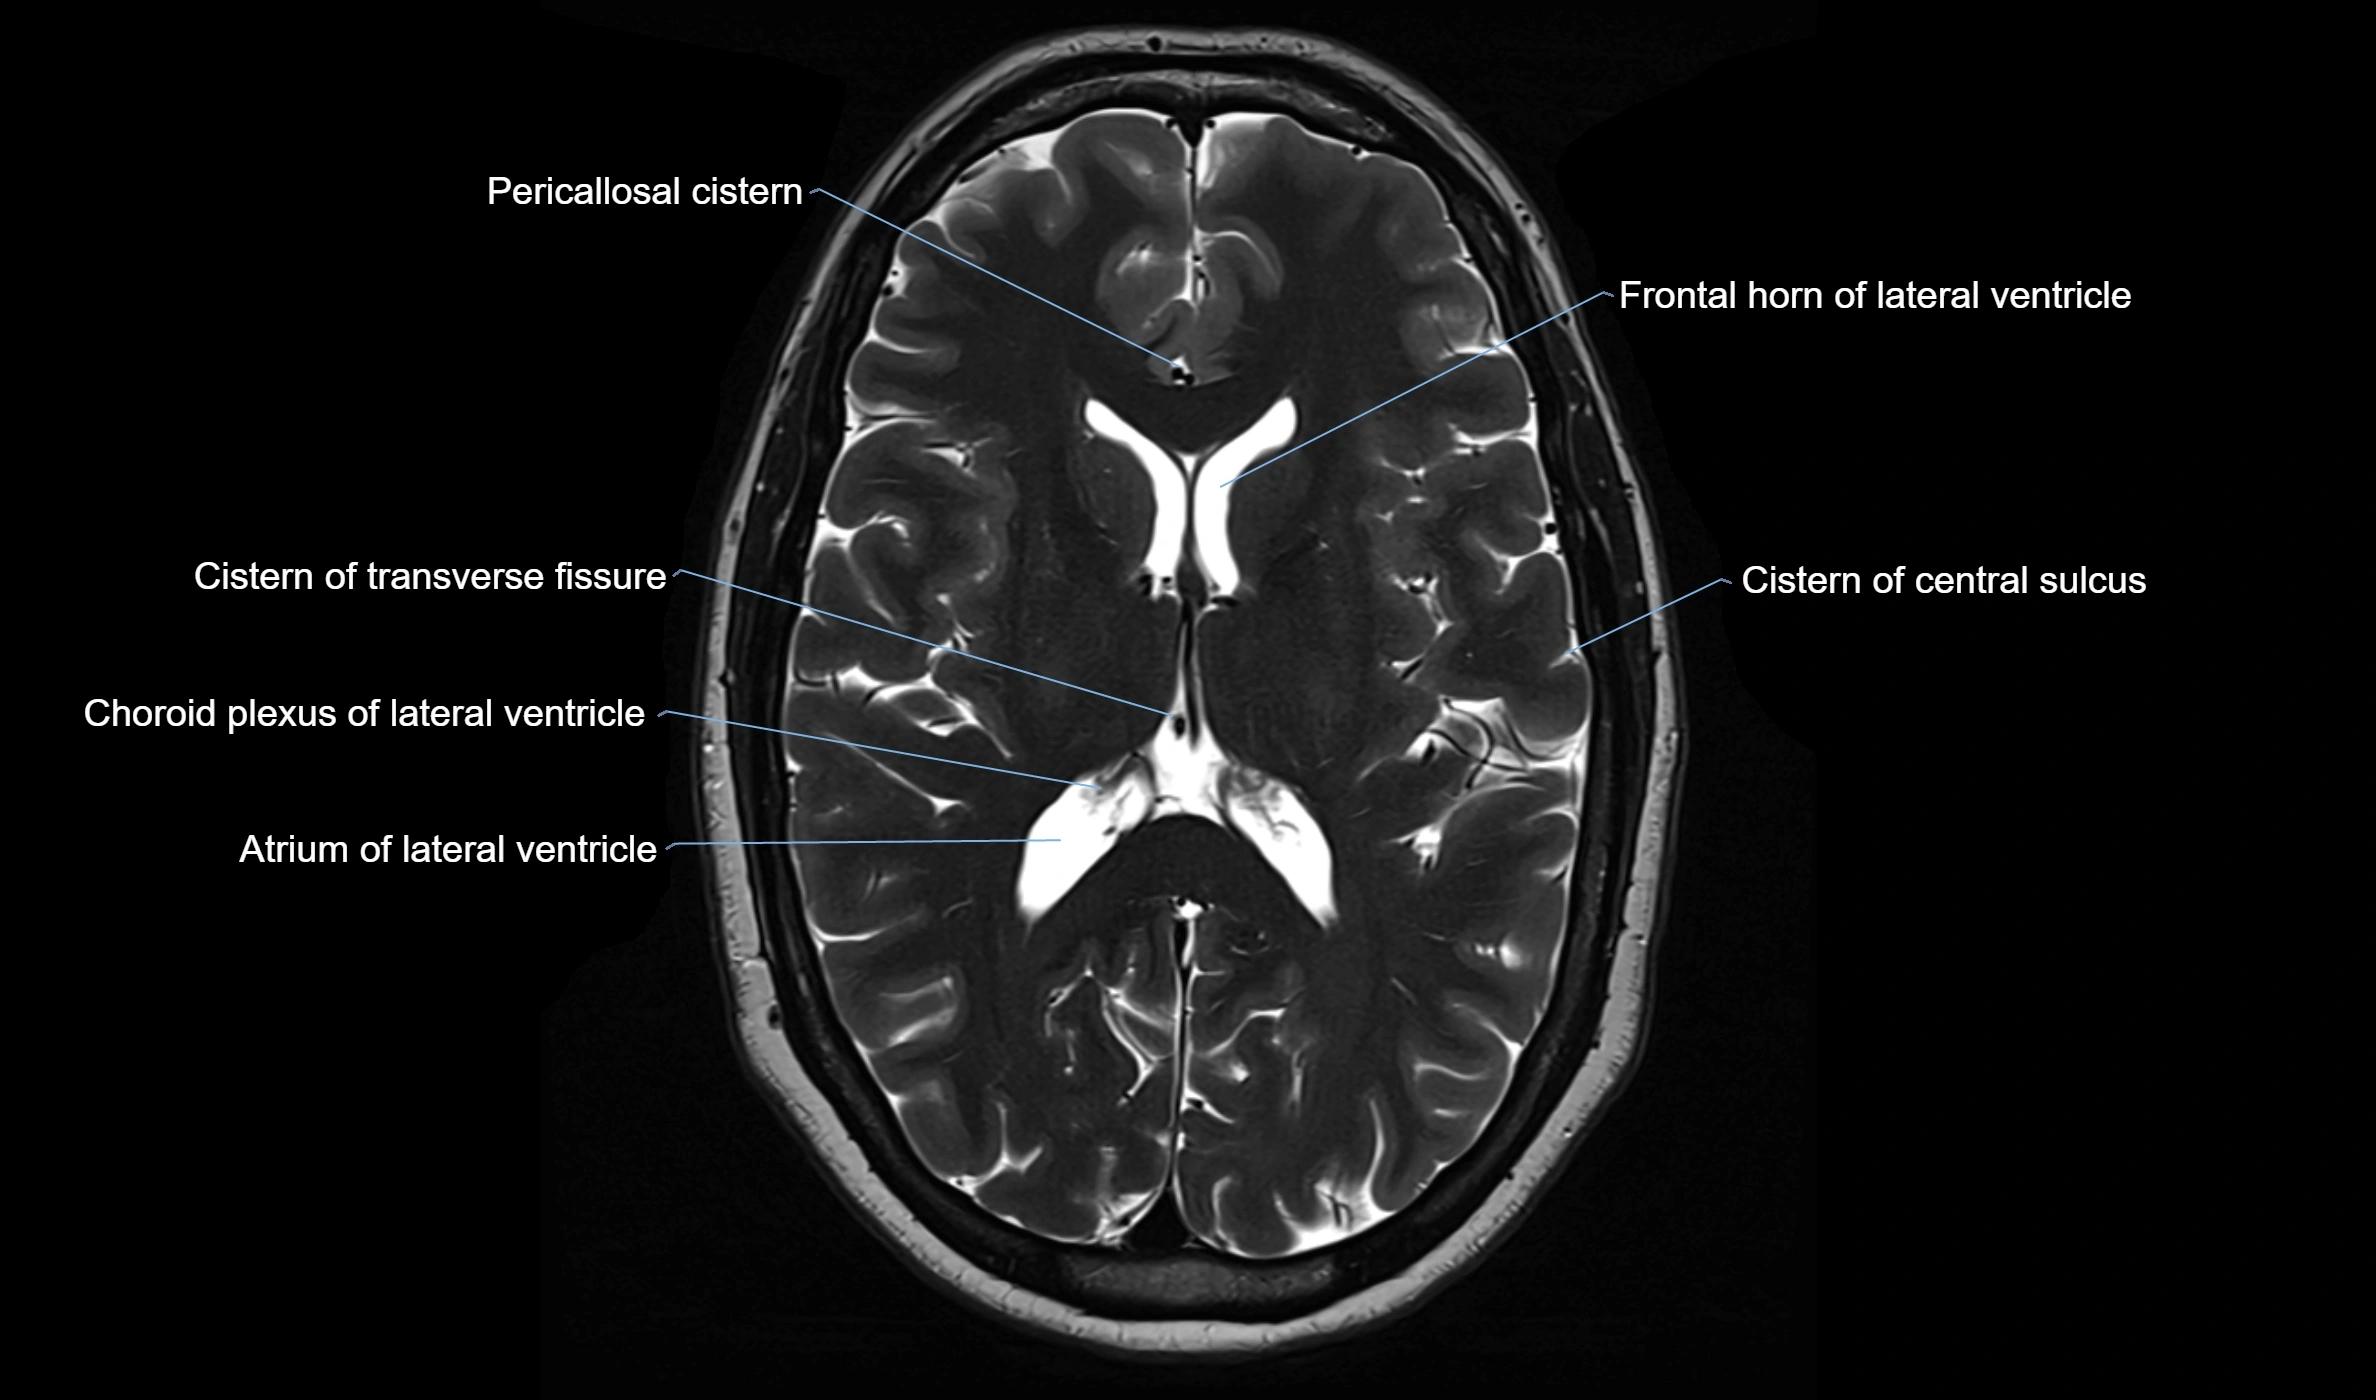

MRI images

image